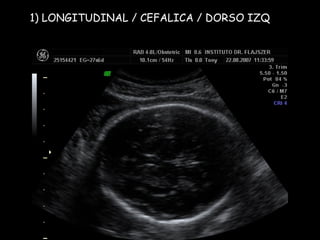

1) LONGITUDINAL / CEFALICA / DORSO IZQ

Apex y estómago: ¿Cerca o lejos del transductor? Lejos Long/Cef/D.izq